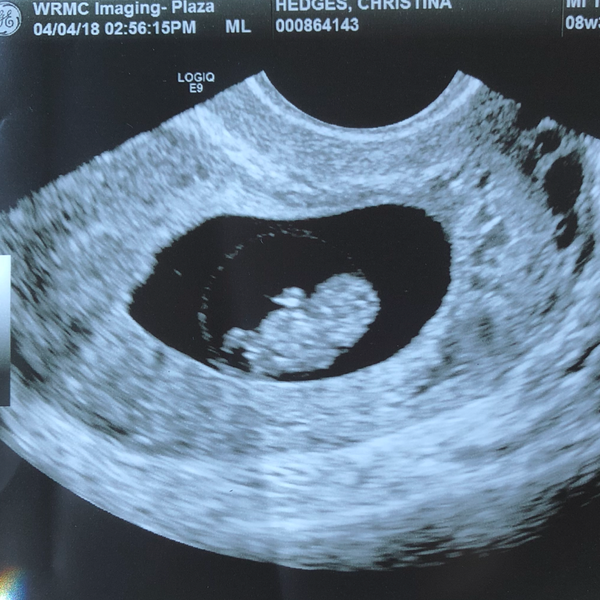

After a little scare (see my last post) we found out our Little is doing great!

I feel like Ramzi is a little tough with this one. He/she is like right in the middle lol

Seeing the little bean and the heartbeat was so relieving!